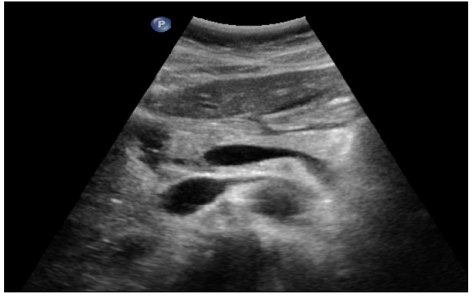

Micronodules

COCHE E. - 2021 - UCL

Cardio-thoracique DES SPECIALITE